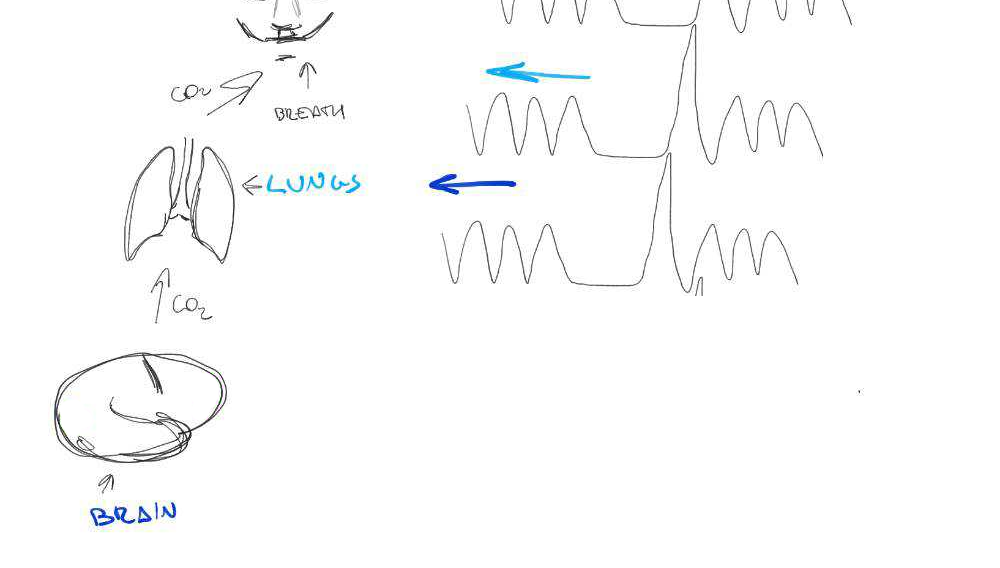

Cerebrovascular Reactivity (CVR) is the response of cerebral vessels to a vasoactive stimulus (e.g. CO2) to provide sufficient O2 to cerebral tissues¹

CVR can be measured during BOLD fMRI experiments with Breath-holds (BH), that induce the subject into a state of hypercapnia²

The vessels dilate → Increase of blood flow → Increase of %BOLD signal

CVR mapping [%BOLD/mmHg] can be obtained through a linear regression analysis using the recordings of exhaled CO2 (reliable proxy of CO2 partial pressure in arterial blood)

BH-induced CVR: Issues

Two problems:

- There's a measurement delay, and regional variations of the physiological delay

- The BH task presents collinear motion to signal of interest

Motion

CO2

BOLD

BH-induced CVR: Issues

Two problems:

- There's a measurement delay, and regional variations of the physiological delay

- The BH task presents collinear motion to signal of interest

Motion

CO2

BOLD